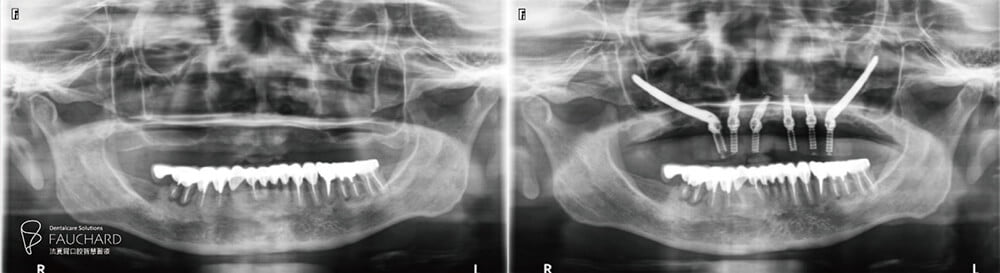

在諮詢階段,醫師會詢問患者的疾病史與用藥史,並進行詳盡全口檢查,在需植牙的牙位拍攝局部X光片(PA)、全口X光片(PANO)、錐狀射束電腦斷層掃描(CBCT)輔助判讀,全方位了解牙齒與牙周的健康情形,必要時先進行相關治療。

這次All-on-4 全口重建案例盤太太,經醫師評估後即使用 2 根顴骨植體來確保全口重建假牙的穩固。(延伸閱讀:【顴骨植體】骨頭不好無法做All-on-4全口重建? Zygoma implant 顴骨植體有解!)

「做好手術,X光一拍,這次骨粉補得滿滿的!」手術當天,盤大哥在旁見證盤太太的手術成果,經過這次療程,盤太太齒槽變得扎實堅固,穩穩地支撐起牙齒。